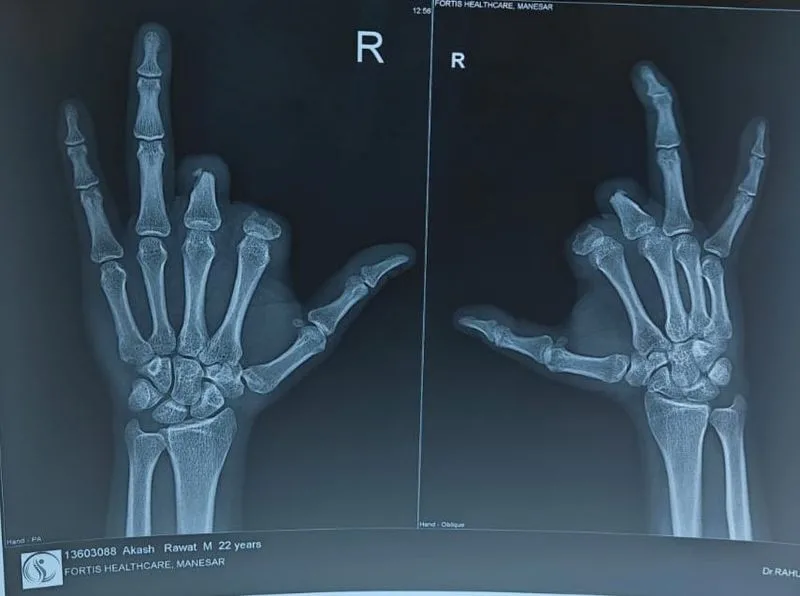

गुरुग्राम के एक स्थानीय होटल में रसोई के नियमित काम के दौरान लगी चोट के कारण पास के एक नर्सिंग होम में आपातकालीन स्थिति में उंगली काटनी पड़ी। लेकिन असली चुनौती तो उसके बाद शुरू हुई। बची हुई उंगलियों के ठूंठों की हड्डी की गुणवत्ता गंभीर रूप से खराब होने के कारण, पारंपरिक पुनर्निर्माण सर्जरी संभव नहीं थी, जिससे उनके हाथ का कार्यात्मक उपयोग पुनः प्राप्त करने की संभावना काफी कम हो गई।

हालांकि, एक मित्र के सुझाव पर आकाश ने ‘बड़े अस्पतालों’ से संपर्क किया, जिससे उसकी किस्मत बदल गई। वह फोर्टिस अस्पताल, मानेसर पहुंचा, जहां डॉ. राहुल जैन के नेतृत्व में एक बहु-विषयक टीम ने एक अभिनव दृष्टिकोण अपनाया – ऑसियोइंटीग्रेशन इम्प्लांट्स को एक विशेष रूप से डिजाइन किए गए कार्यात्मक प्रोस्थेसिस के साथ मिलाकर उपचार करना। पारंपरिक प्रोस्थेटिक्स के विपरीत, यह उन्नत तकनीक जीवित हड्डी और टाइटेनियम इम्प्लांट के बीच सीधा संबंध स्थापित करती है, जिससे बेहतर मजबूती, नियंत्रण और निपुणता के लिए एक स्थिर और टिकाऊ इंटरफ़ेस बनता है।